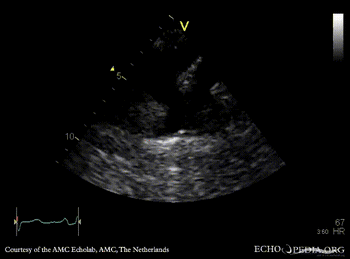

E00363.jpg

Conituous-wave signal of coarctatio aortae, sawtooth phenomenon